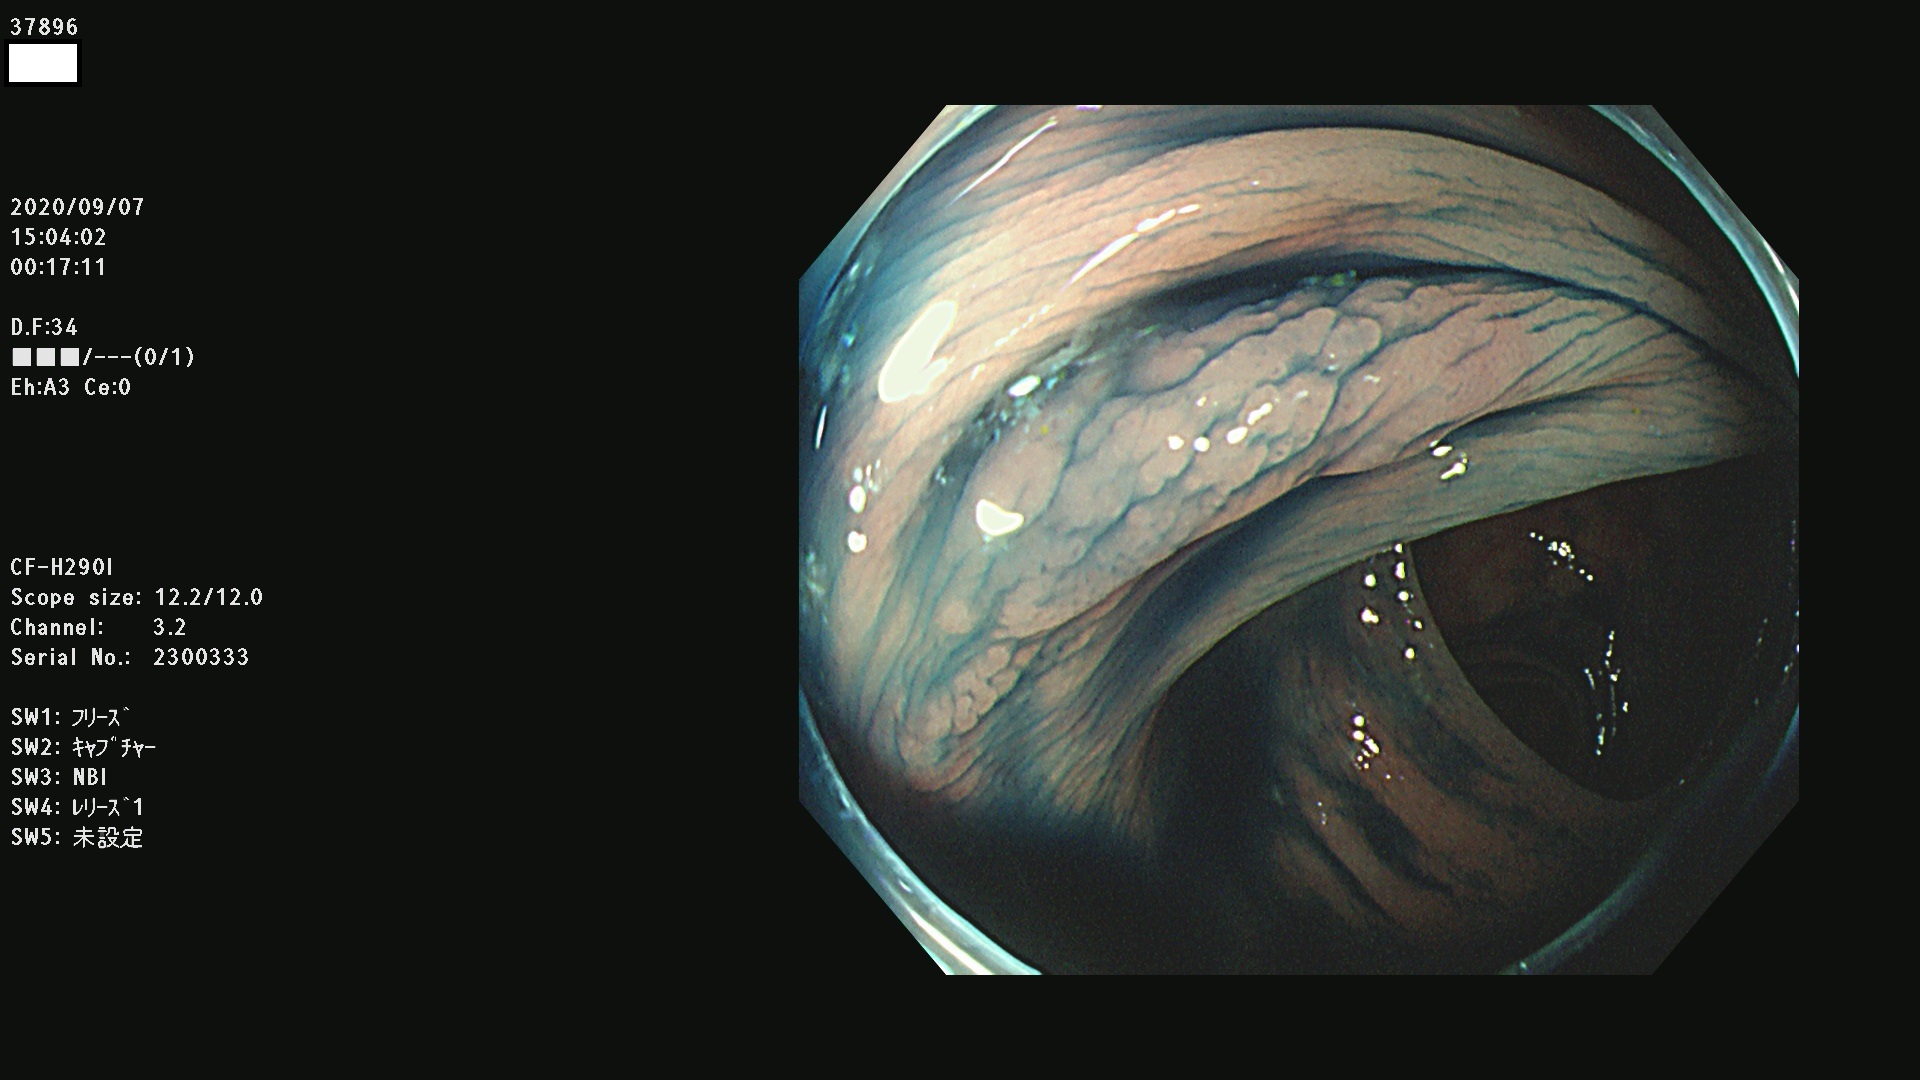

腺腫発見率 75 % (カルテ番号 37800〜37899の100名の方の検査結果で集計)大腸癌検診最新情報

以下のカルテ番号の方に腺腫(Adenoma,Group3〜5)が見つかりました(集計法)

37800(SSAPのみ) 37801 37802 37803 37804 37805 37806 37807 37808 37809(SSAPのみ) 37810 37811 37812 37813 37814 37815 37817 37818 37819 37820 37821 37822 37824 37825 37826 37827 37828 37829 37832 37833 37836 37837(SSAPのみ) 37839 37840 37842 37844 37845(SSAPのみ) 37847 37849 37850 37851 37852 37853(SSAPのみ) 37855 37856 37857 37860 37861 37862 37863 37864 37867 37868 37871 37874 37876 37877 37879 37880 37881 37882 37883 37886 37887 37888 37889 37890 37891 37892 37893 37894 37896 37897 37898 37899

発見困難で危険性の高い平坦型病変(上記100名より抽出) ![]()